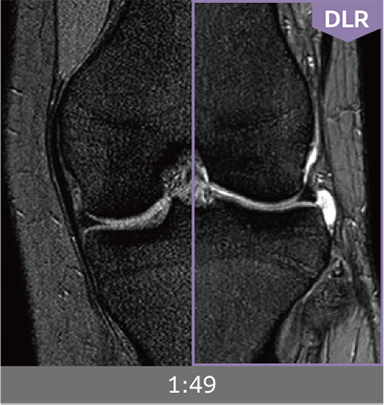

Combining high-speed imaging technology with Deep Learning reconstruction technology*3, Advanced Reconstruction with Deep Learning Synergy DLR, enables shorter exams and reduces image noise.

Images can be obtained at high speed by combining two proprietary technologies: IP-RAPID, which reduces imaging time while maintaining image quality, and Synergy DLR, which uses deep learning technology*6 to improve image quality

Under-sampling reduces imaging time, and iterative reconstruction with IP-RAPID reduces noise and artifacts.

In addition, Synergy DLR, an image reconstruction technology utilizing deep learning technology, further eliminates noise and produces images that are easier to use in making a diagnosis.